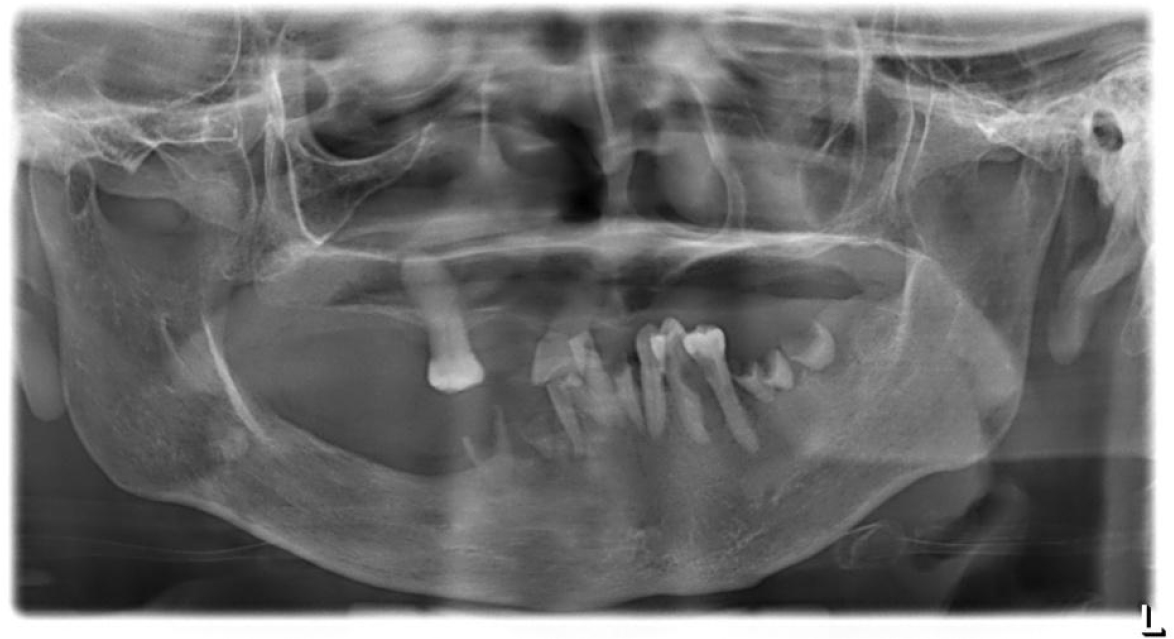

When the patient presented to the Department of Oral and Maxillofacial Surgery, an initial panoramic radiograph revealed multiple retained root tips and missing teeth (Fig. 1). The patient was unable to maintain good oral hygiene because of limited mouth opening. Extra-oral examination revealed a 12-mm mouth opening and facial asymmetry with an anterior crossbite due to maxillary deficiency (Figs. 2 and 3A, 3B, respectively). Underdevelopment of the maxilla was associated with muscle contracture from the previous free flap. Intraoral examination revealed multiple missing teeth, retained roots, and loss of the buccal vestibule.